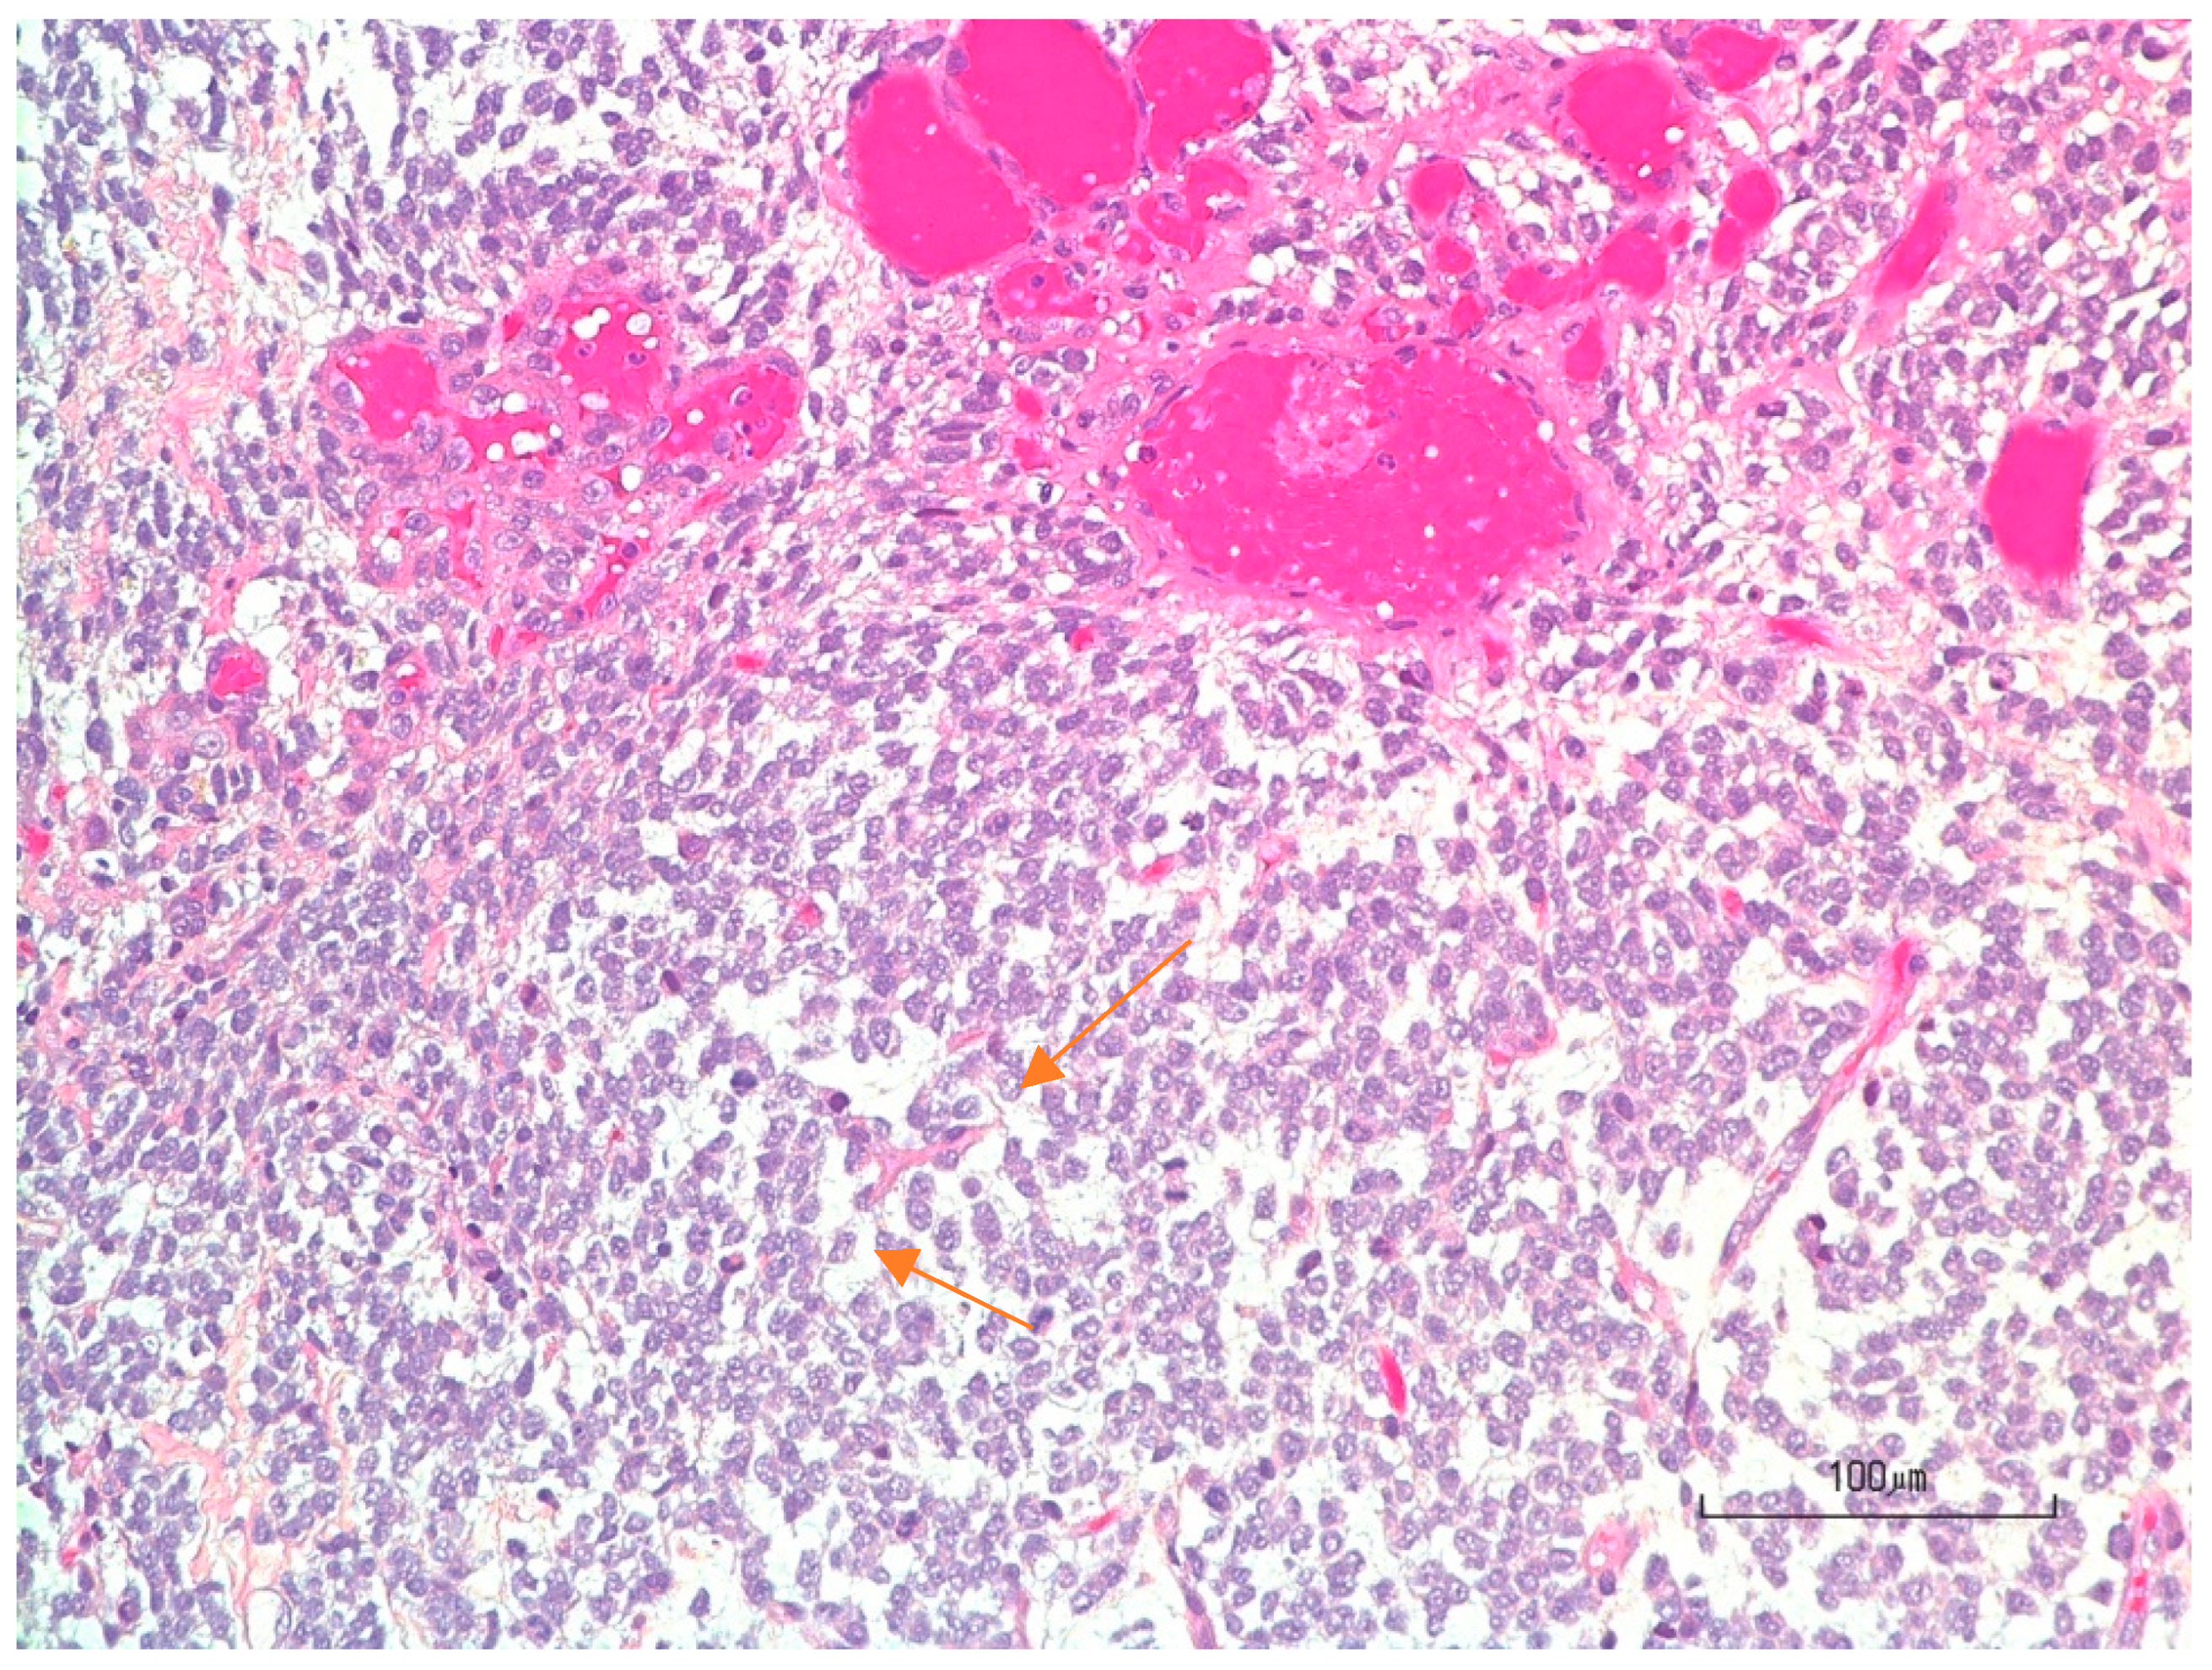

3.4. Pathology